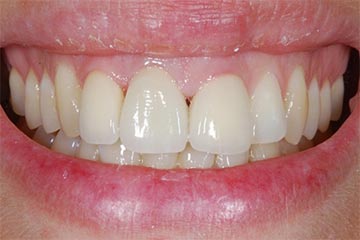

Con protesi fissa superiore e protesi fissa inferiore

I denti irrecuperabili dell'arcata superiore ed inferiore del paziente di anni 65

sono stati sostituiti da 10 impianti, cioè protesi radicolari endo-ossee che sostengono le protesi fisse superiore ed inferiore.